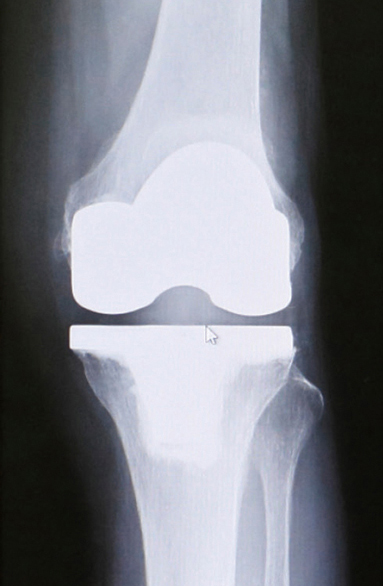

人工膝関節単顆型置換術後

のレントゲン